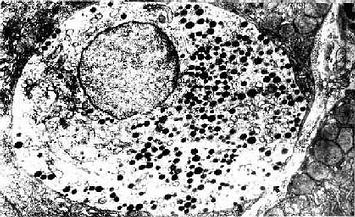

图12-23 小鼠肠腺内的APUD细胞 ×13200

↑基膜 (上海医科大学电镜室供图)

胃肠内分泌细胞大多单个地夹于其它上皮细胞之间,呈不甚规则的圆锥形。基底部附于基膜,并有基底侧突与邻近细胞相接触。胞质中含一些粗面内质网与高尔基复合体。细胞最显著的形态特点是底部胞质中含大量分泌颗粒,故又称基底颗粒细胞(basal granular cell)(图12-23)。分泌颗粒的大小、形状与电子密度依细胞类型而异。绝大部分细胞具有面向管腔的游离面,称开放型,游离面上有微绒毛伸出。此型细胞对管腔食物的刺激和pH变化等化学信息有较强的感受性,从而引起其内分泌活动的变化。少数细胞的顶部被相邻细胞覆盖而未露出腔面,称封闭型,主要受胃肠运动的机械刺激或其它激素的调节而改变其内分泌状态(图12-24)。分泌颗粒中含肽和(或)胺类激素,大多在细胞基底面释入固有层中的毛细血管,经血循环运送并作用于靶细胞;少数激素被释放后可直接作用于邻近细胞,以旁分泌方式调节靶细胞的生理功能。在HE染色切片上,胃肠内分泌细胞不易辩认;用铬或银盐浸染,少数种类的细胞可因其分泌颗粒具嗜铬性、嗜银性或亲银性而被显示。目前主要用免疫组织化学方法来显示这些细胞。